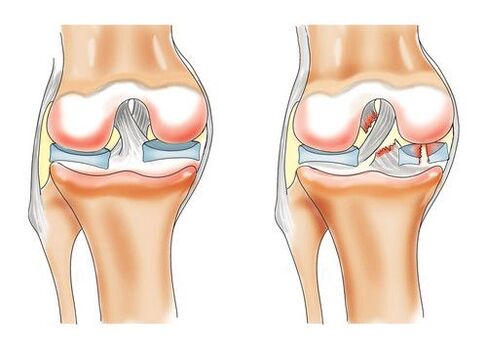

Die Entwicklung einer Gonarthrose des Kniegelenks wird durch negative Prozesse im hyaliner Knorpel begünstigt, vor allem durch eine schlechte Durchblutung kleiner Knochengefäße. Der Mangel an Nährstoffen und Sauerstoff, der durch den Lymphfluss transportiert wird, führt zur Zerstörung der äußeren Knorpelschicht des Knies.

Im Anfangsstadium ist die Krankheit äußerst schwer zu erkennen. Die Verformung des Gelenks erfolgt langsam, bis der Glasknorpel in den Prozess einbezogen wird. Die anatomische Struktur des Bandes verändert sich. Es kommt zur Trübung, das Gewebe wird dicker, dünner und reißt in alle Richtungen. Das Ergebnis der Pathologie kann das vollständige Verschwinden des Knorpels sein, was zu neuem Wachstum des Knochengewebes und einer irreversiblen Krümmung des Knies führt.